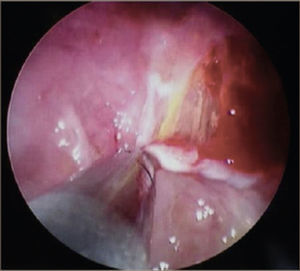

La toracoscopía médica puede ser realizada en sala de endoscopía o en pabellón, con anestesia local y sedación e.v. No requiere intubación. Se accede a la cavidad pleural por un portal de entrada de 10mm, no requiere de estadía en sala de postoperados en forma obligada. Se drena en forma segura todo el derrame contenido en la cavidad pleural y luego se inspecciona la cavidad. Permite tomar biopsias grandes bajo visión directa sobre la pleura parietal, pulmón y diafragma que permitirán hacer estudios moleculares y de inmunohistoquímica al tejido y además permite efectuar pleurodesis en el mismo procedimiento44. (Figuras 5–7).